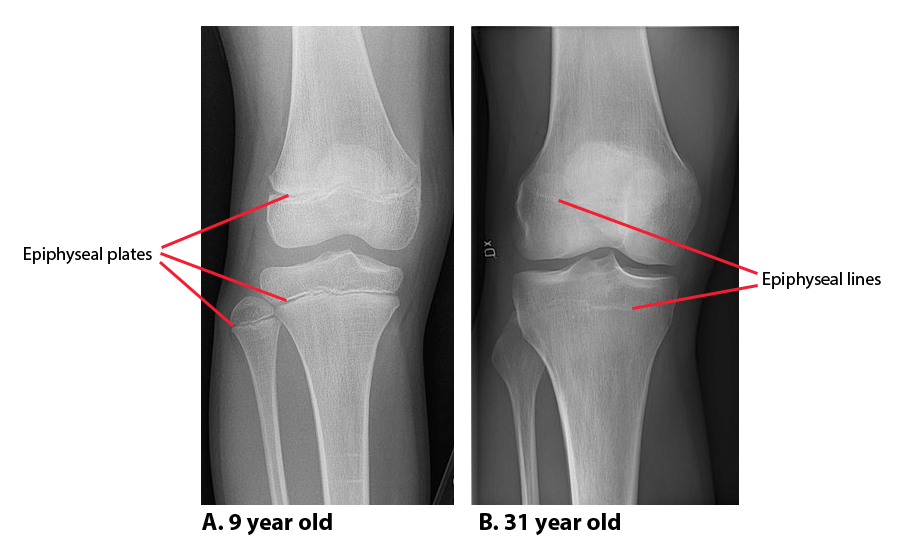

Xray or MRI the knees (the former is simpler), there will be an opening above the kneehow do i know if my growth plates are closed